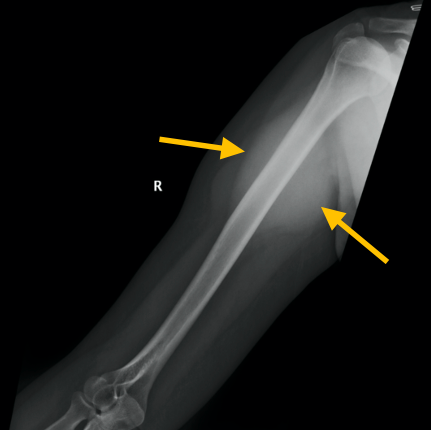

Round Cell Liposarcoma is a malignant, or cancerous, soft-tissue sarcoma that most commonly occurs in the deep tissues of the thigh, or other extremities. It is fairly aggressive and has a greater potential for metastasis.